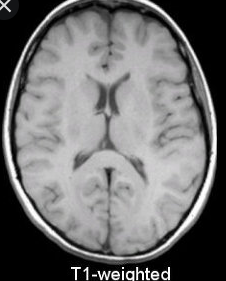

MRI 건강보험 적용